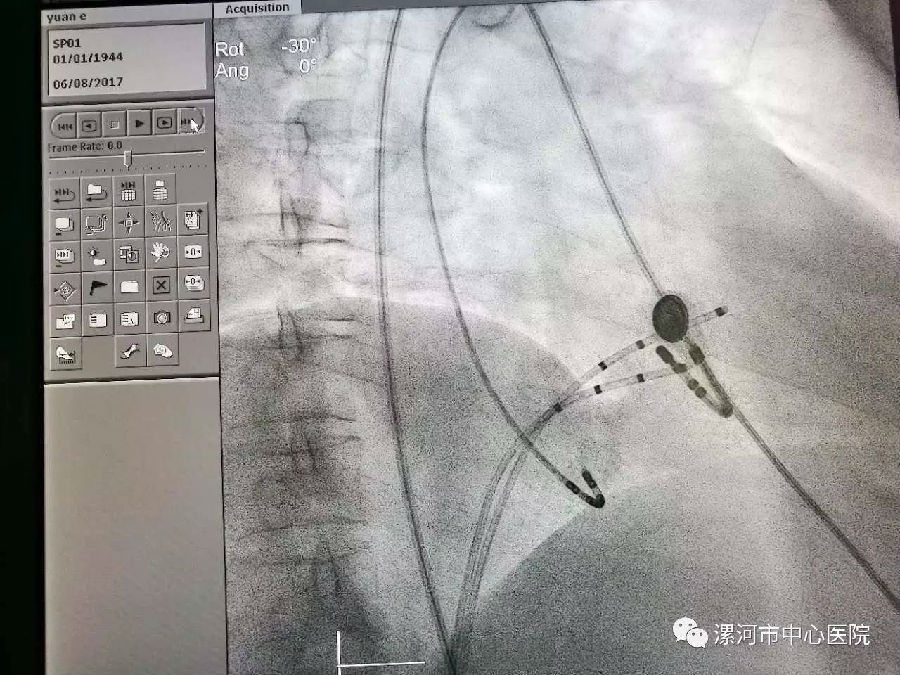

图为消融导管、电极在心脏内走行。因病人存在多条心脏内异常传导通路,心内结构变异较多,大大增加了手术难度。